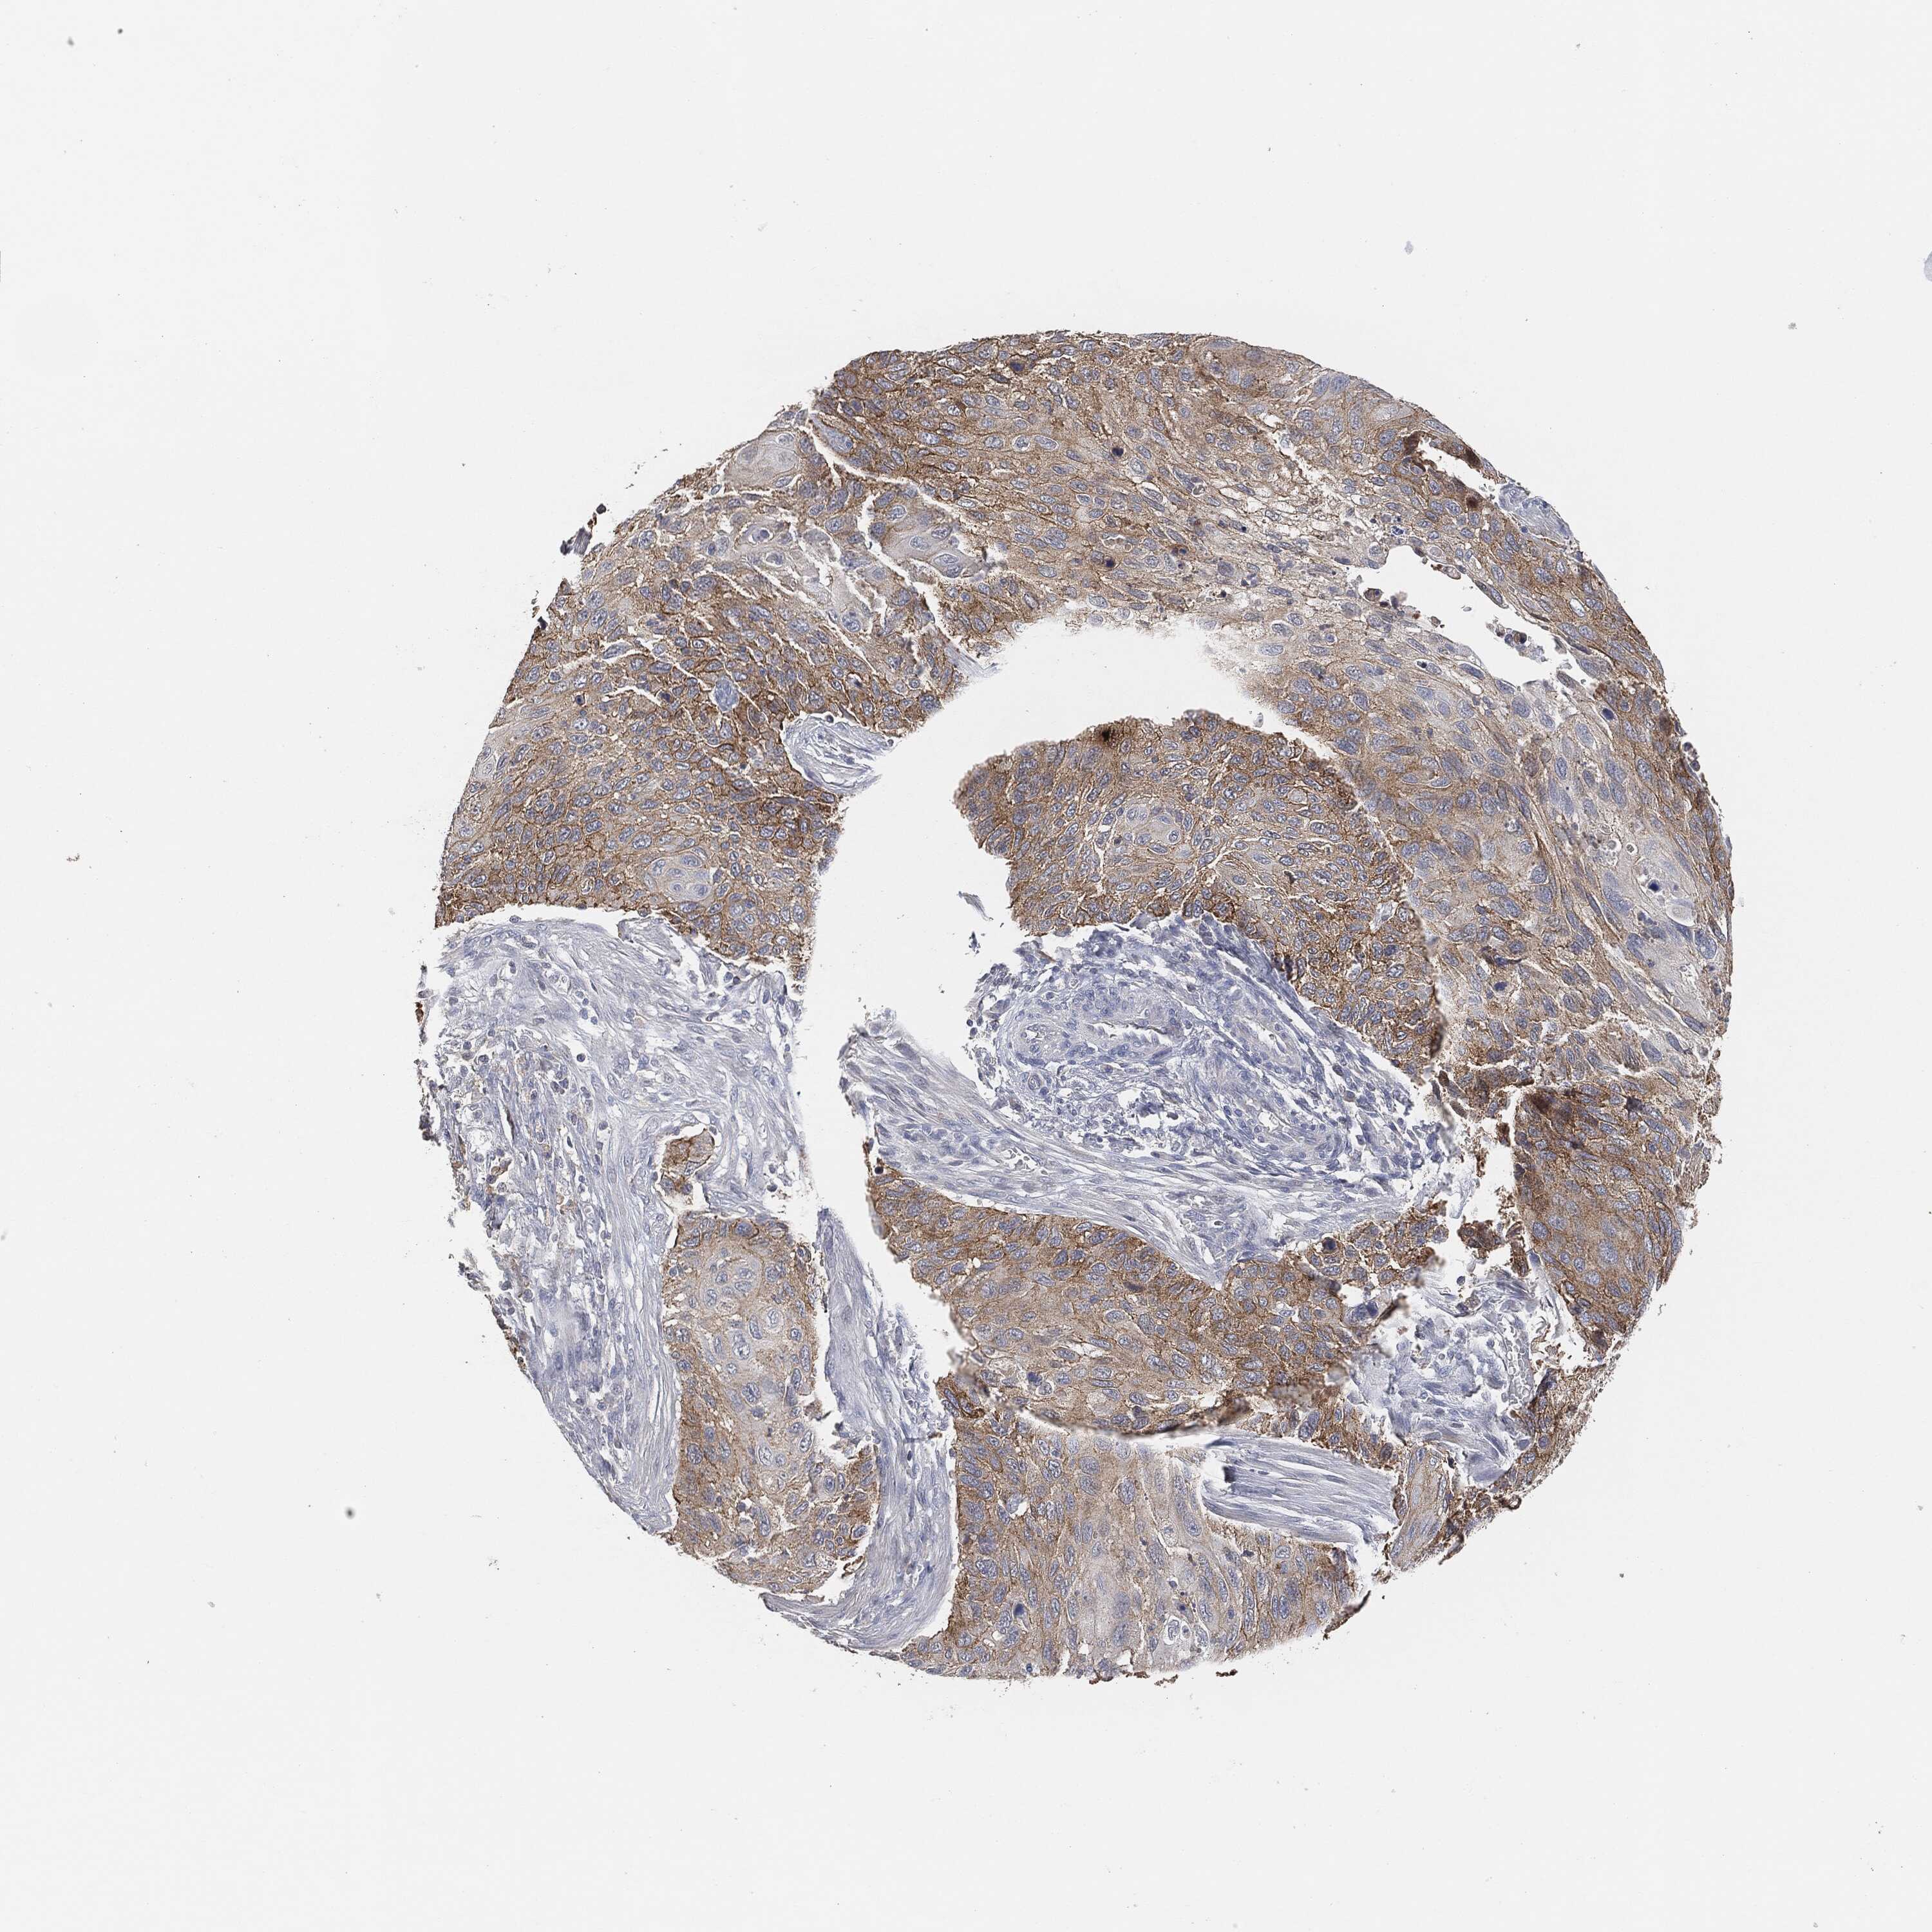

CERVICAL CANCER - Protein expressioni

A mouse-over function shows sample information and annotation data. Click on an image to view it in a full screen mode. Samples can be filtered based on level of antibody staining by selecting one or several of the following categories: high, medium, low and not detected. The assay and annotation is described here.

Note that samples used for immunohistochemistry by the Human Protein Atlas do not correspond to samples in the TCGA dataset.

Antibody stainingi

Antibody staining in the annotated cell types in the current human tissue is reported as not detected, low, medium, or high, based on conventional immunohistochemistry profiling in selected tissues. This score is based on the combination of the staining intensity and fraction of stained cells.

Each image is clickable and will lead to virtual microscopy that enables deeper exploration of all samples and also displays staining intensity scores, fraction scores and subcellular localization as well as patient and tissue information for each sample.

Adenocarcinoma, NOS